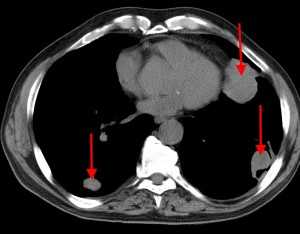

Спиральная КТ с контрастным усилением позволяет законтрастировать просвет легочных сосудов и увидеть тромб в их просвете. У молодого мужчины после межконтинентального перелета возникла острая боль в груди и нарушение дыхания. КТ визуализирует тромб в артерии переднего сегмента верхней доли левого легкого ( LA 2) и артерии переднего сегмента верхней доли правого легкого ( RA 2).